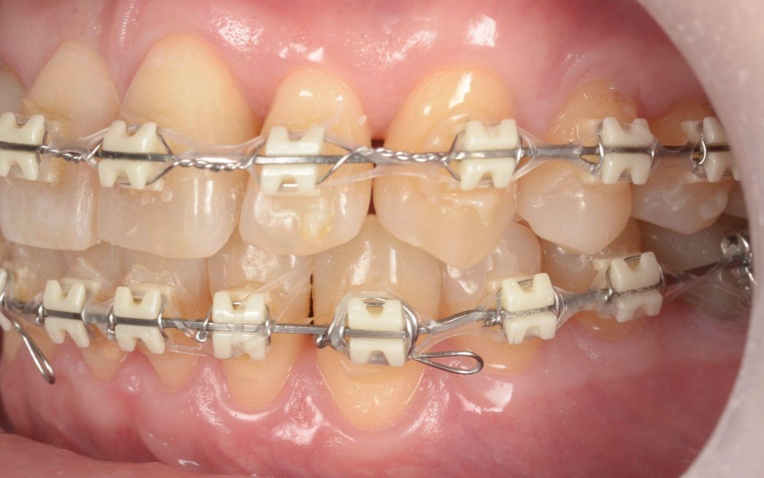

まず、ワイヤー矯正装置を用いた矯正治療を開始します。

折れている歯を一時的に利用しながら、受け口傾向にある噛み合わせが改善するよう、歯の位置を少しずつ調整していきました。

矯正治療中は定期的に来院いただき、装置の調整を行います。

歯や歯茎の状態、噛み合わせの変化を確認しながら、目標とする歯並びと噛み合わせに近づくよう治療を進めました。

治療中